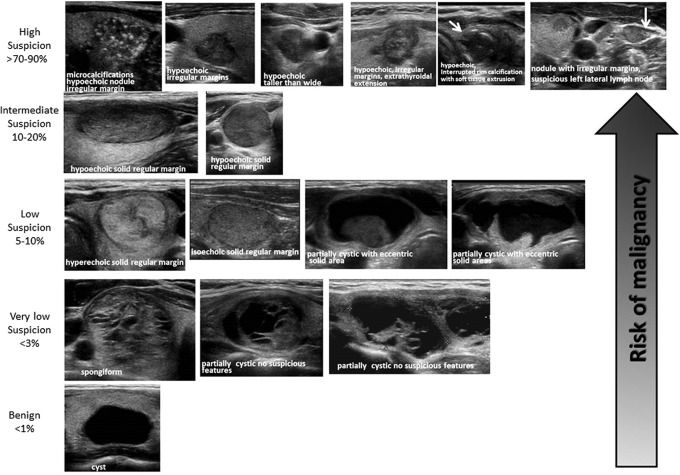

- Malignant Thyroid abnormalities:

- Hypoechogenicity, cystic change, irregular margins, calcifications, taller greater than wide, vascularization, extrathyroidal extension.

- Two popular scoring systems to predicting malignancy:

- The American College of Radiology Thyroid Imaging, Reporting and Data System (TI-RADS) scoring system:

- Figure 39. TI-RADS

- American Thyroid Association (ATA) visual patterns:25

- Figure 40. ATA Nodule Sonographic Patterns and Risk of Malignancy (Used with permission. License no: 4463231228489)

- Benign Thyroid abnormalities:

- Spongiform nodule (microcysts > 50% of nodule), halo sign, and absent vascularization